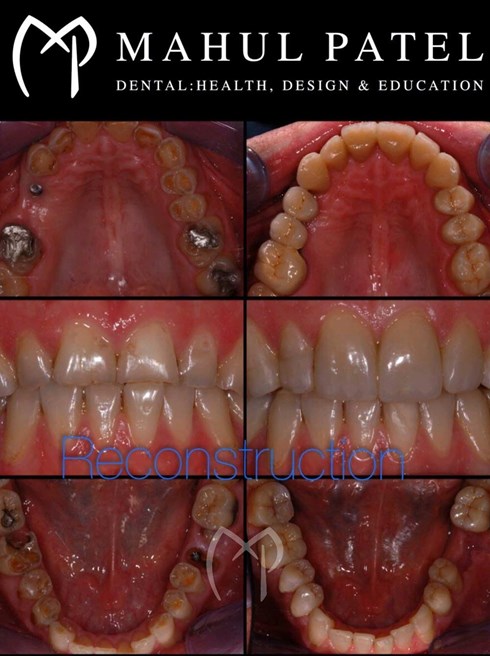

• Provision of full mouth reconstruction (fixed, removable and implant)